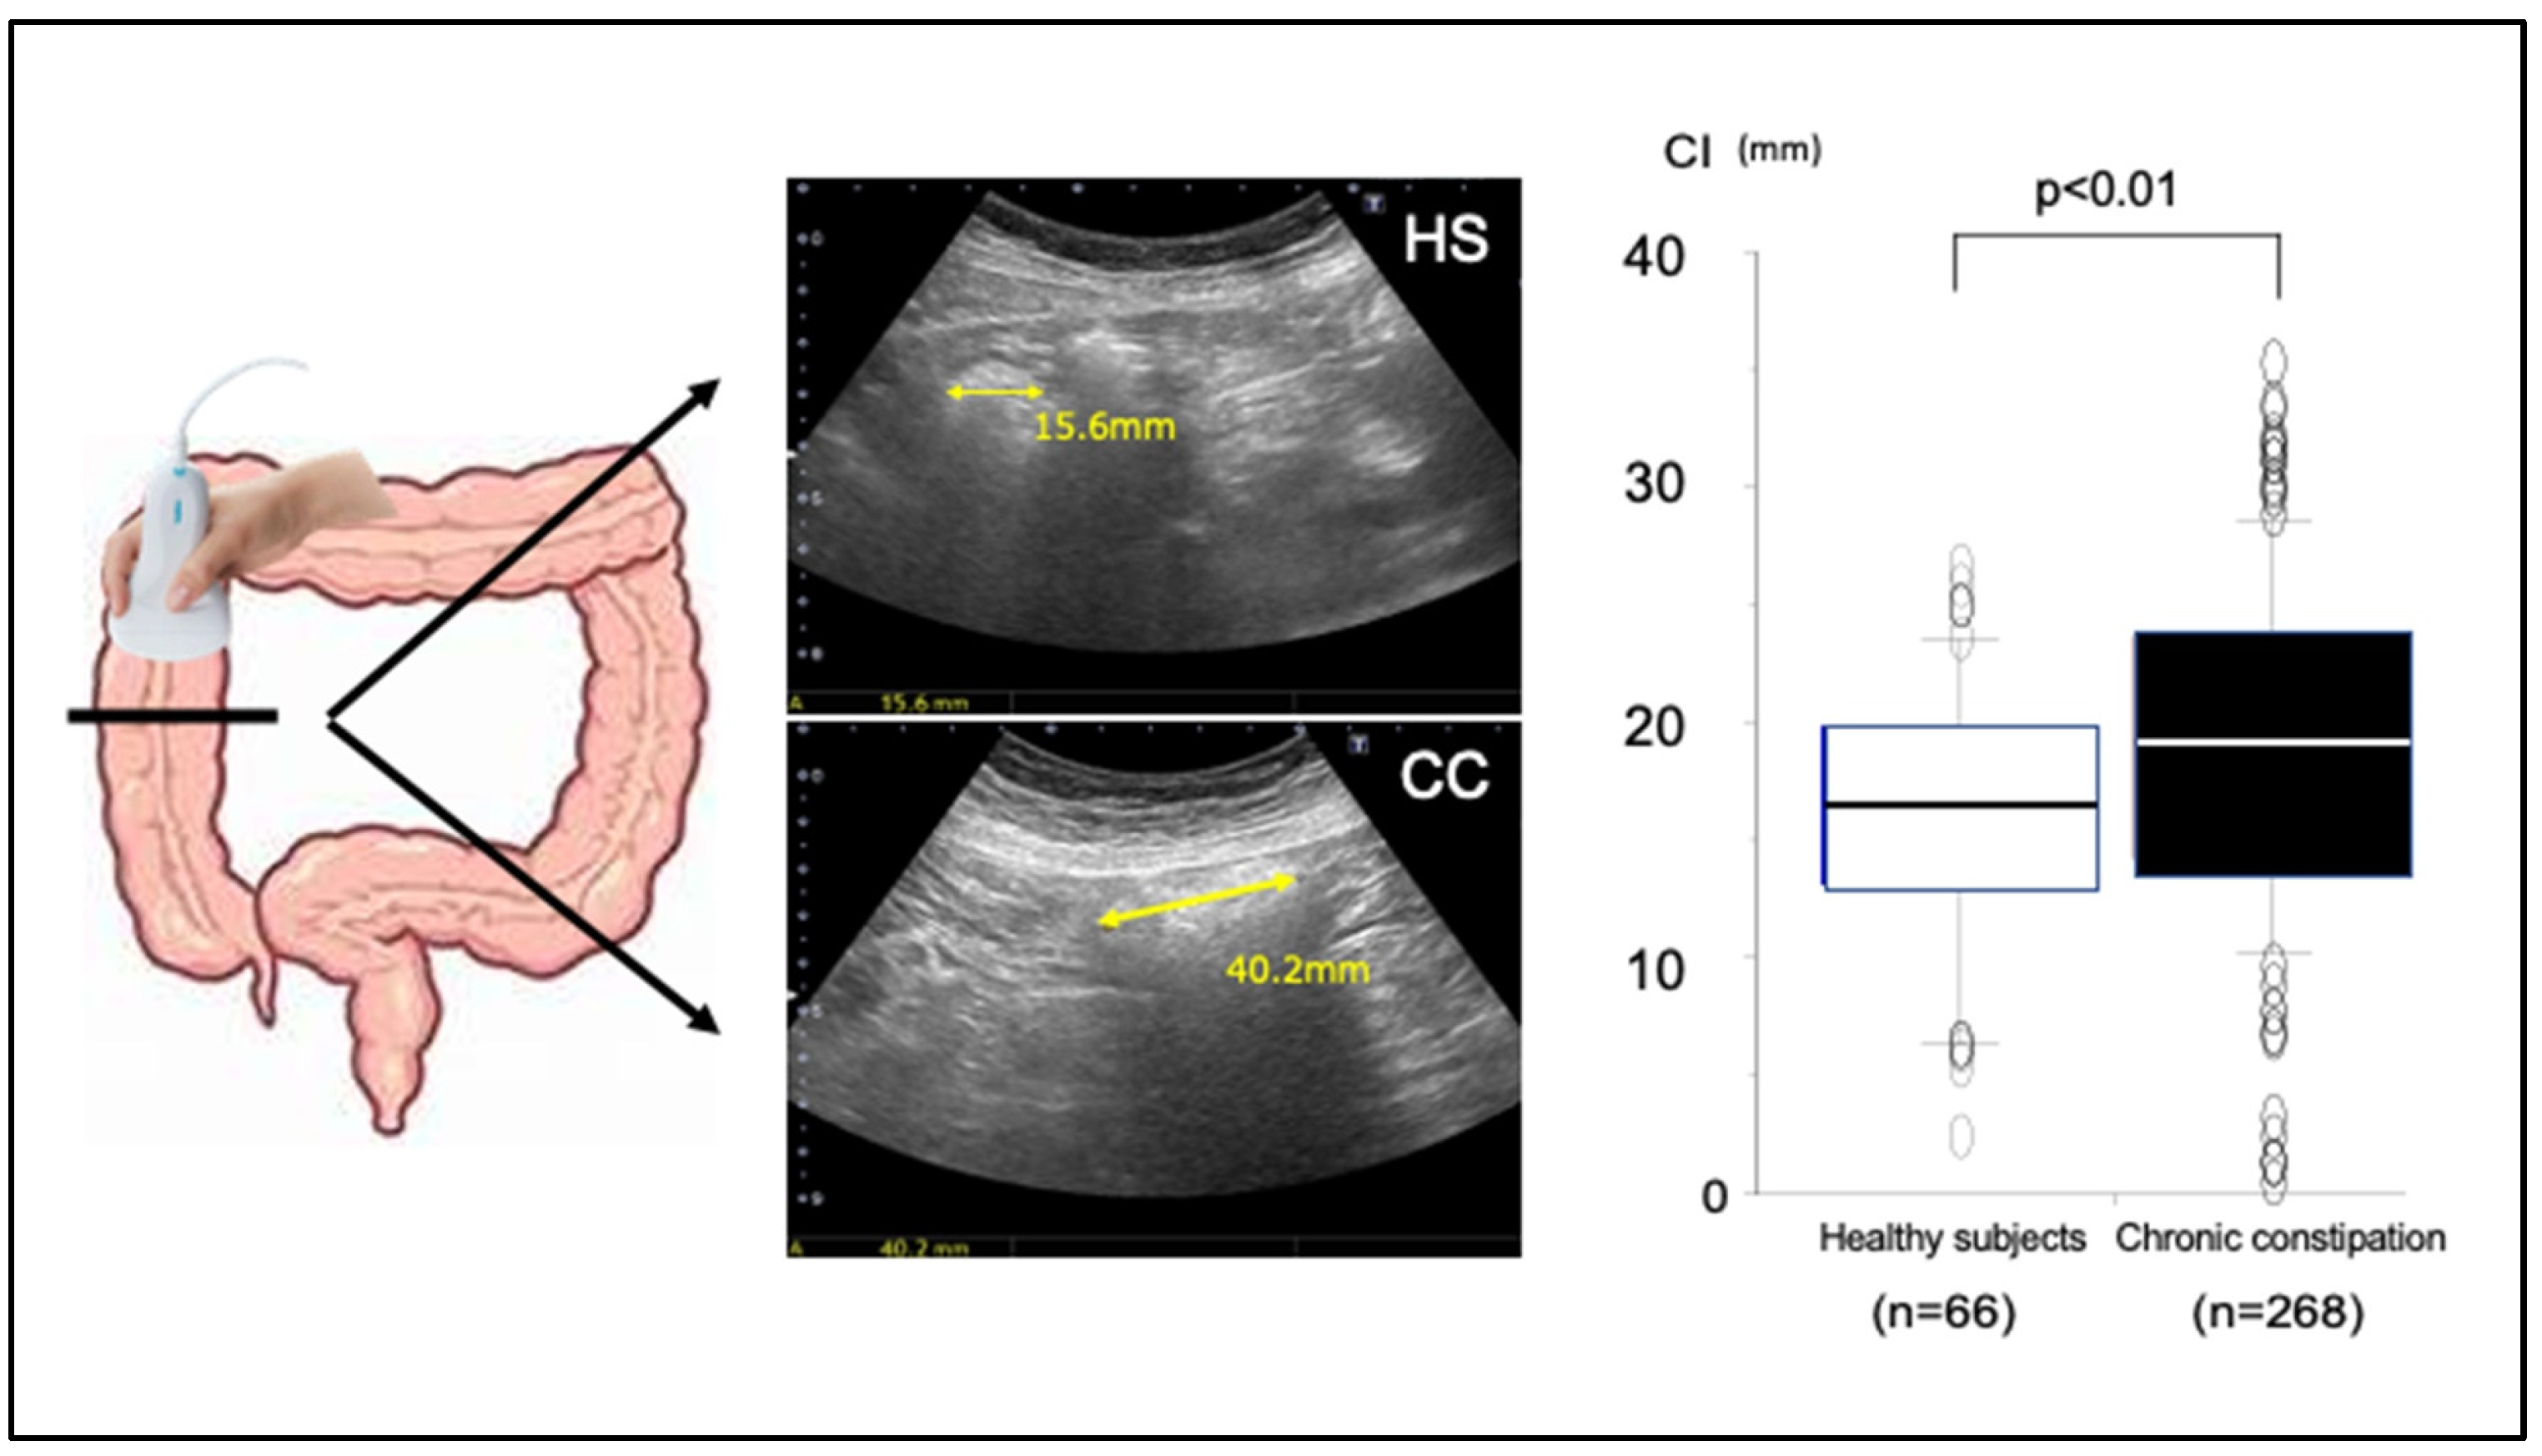

5. Clinical Application of TUS for Evaluating the Colonic Transit Time

Despite the development of scintigraphy and radiopaque marker methods for functional assessment of the colonic transit time, the challenges posed by equipment costs, examination duration, and X-ray exposure have impeded their integration into routine clinical practice in Japan. Recently, we reported that TUS can be used for indirect estimation of the colonic transit time through the measurement of colonic lumen diameter [37]. In that study, we initially identified a notable correlation between the colorectal luminal diameter as measured by TUS and computed tomography. Next, using the colorectal luminal diameter obtained by TUS, we derived two essential parameters for assessment of colorectal motility function: (i) the mean transverse colonic diameter (constipation index (CI) = (ascending colon + transverse colon + descending colon + sigmoid colon + rectum)/5) and (ii) the ratio of the luminal diameter of the left-sided and right-sided colon (Left/Right ratio (L/R) = (descending colon + sigmoid colon)/(ascending colon + transverse colon)) [37]. For a long segmental colon such as the ascending colon, measurements were taken at the oral, central, and anal regions and the mean value used. A comparison of these TUS parameters in 66 healthy subjects and 268 chronic constipation patients revealed a significantly higher CI with chronic constipation (Figure 7) [37]. The relationship between the CI obtained by TUS and the colonic transit time obtained by the radiopaque marker method was also examined in 45 eligible patients; there was a significant positive correlation between the two variables, which indicates that patients with a higher CI have longer colonic transit times [37].

Figure 7. Comparison of the constipation index (CI) between 66 healthy subjects and 268 patients with chronic constipation. CI values for patients with chronic constipation were significantly higher than those for healthy subjects. From Manabe et al. [41] modified.